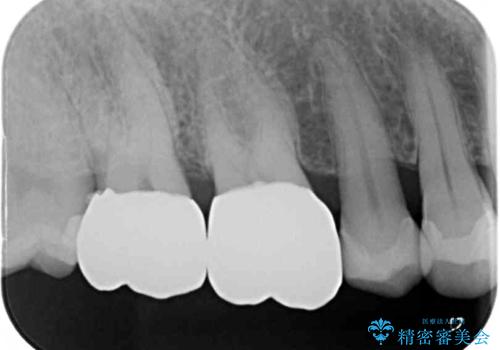

- 奥歯の銀歯をセラミックの白い歯にして、しみる症状も改善したいとのことで来院された患者様です。

知覚過敏の症状が強い歯と、銀歯の範囲や銀歯の下のむし歯が大きい歯は、インレー修復では対応が難しいためオールセラミッククラウンで、インレー修復で対応が可能な歯ではセラミックインレーにて修復することとしました。

知覚過敏の症状はなくなり、希望通りの白い歯になったと、患者様は大変満足されました。